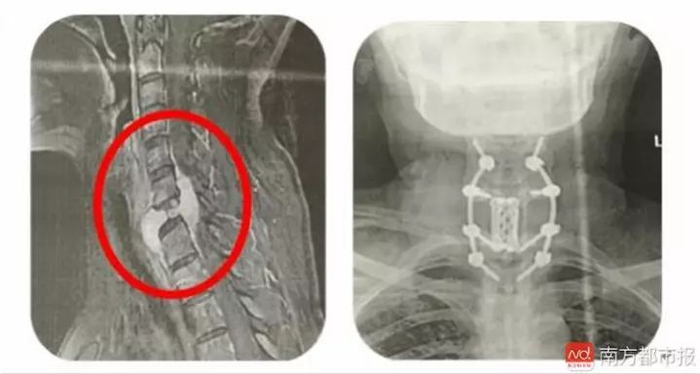

苏女士在中山市中医院脊柱科就诊时,医生在颈椎CT及MRI检查中,发现她的第7节段颈椎有个肿瘤,颈椎管狭窄,脊髓损伤。随后,该院脊柱肿瘤组团队为其进行了一场手术,术后苏女士肌力立刻得到了明显的改善,一周内已经能够独立行走。